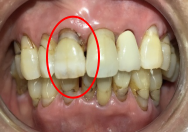

女性Yさん 60代(オールセラミック冠)

以前治療した右下の犬歯が、虫歯になり色が変わってきているので、治したい。

治療内容

根管治療をし、オールセラミック冠を被せました。

所感

神経が取り除かれ、歯自体が変色し、虫歯になっていました。根管治療をし、ファイバーコアを入れ、オールセラミック冠を被せました。

オールセラミック冠(失活歯)1本:¥104,500(税込)

Before

After